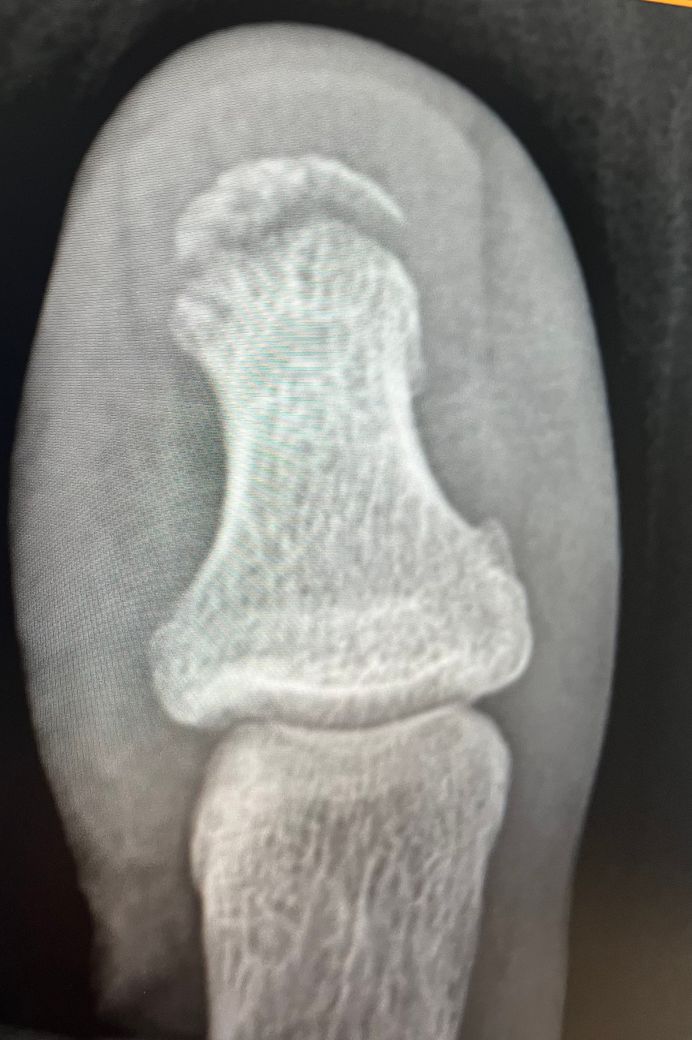

발가락 개방성 골절 골수염 가능성 문의

안녕하세요. 사진과 같이 무거운 물체가 찍어서 발톱 뿌리 부분이 들리고 살이 찢어져 피가 많이나는 외상과 원위지골 개방성 골절 진단 받았는데요. 수술은 안했고

뼈가 드러났는진 모르겠습니다.

사진은 첫번째 두번째가 일주차 나머지는 3주차 현재입니다. 2주차 때 코반 푸니까 갑자기 피부가 빨갛게 변했는데 일주일이 지나도 그대로네요 이건 혈관 문제고 염증은 아니죠.?

• 1번 째 사진

• 2번 째 사진

• 3번 째 사진

• 4번 째 사진

• 5번 째 사진

• 6번 째 사진

• 7번 째 사진